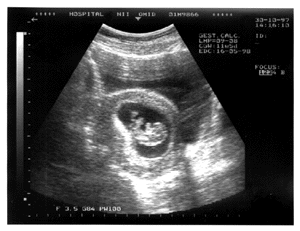

Растем! Вес малыша уже около 7 граммов. Внешний вид плода все еще необычен: руки выглядят более длинными, чем ноги (поскольку и развиваются быстрее). Очень впечатляют размеры головы. Однако не волнуйтесь - к моменту родов эти диспропорции практически исчезнут (ведь сколько-то лет и месяцев назад Вы сами выглядели почти также). На этой неделе завершается формирование грудины. Продолжают развиваться пальцы кистей и стоп. Из "новостей": начинается образование радужки (так называют часть глазного яблока, по цвету которого мы обычно судим о цвете глаз человека). Так выглядит плод на сонограмме:

Так может выглядеть плод на сонограмме.